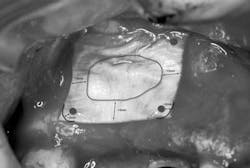

1. A full-thickness flap is reflected to gain access to the lateral wall of the maxillary sinus (Fig. 1). In this area the bone is normally very thin, usually less than 1 mm.Fig. 34. The sinus membrane is separated from the bony wall. Perforations of the membrane occur frequently during this phase. To increase safety and reduce complications, the air-driven sonic handpiece is used, coupled with the discoid insert. The insert is activated (vibrating and irrigated by the water spray) and then placed between the lateral bone wall and the Schneiderian membrane (Fig. 4).